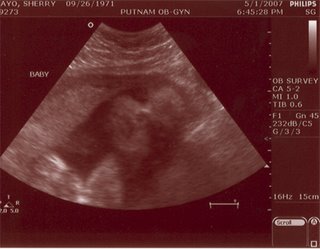

--Junior looks to be bit better than 4 lbs with a very good tummy circumference measurement -- whatever that is good for. We just don't know how long Junior is but I do know that Junior has a foot fetish and tries hard to grab for its feet, frequently -- which is obviously getting harder for Junior to accomplish -- hence all that squirming on my right-side from bottom to top. (*You'd think Junior a PISCES)